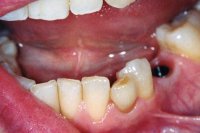

Gemeinsam im Gespräch mit der Patientin wurde die Operation beschlossen. Allerdings war vorgängig noch etwas zu regeln: Die Prämolaren hatten kein angewachsenes Zahnfleisch (siehe Mukogingivalchirurgie), was für den operativen Zugang zu den Wurzeln einen negativen Aspekt für die Abheilung bedeutete.

Also wurde vorgängig ein Zahnfleischtransplantat einoperiert.

Jetzt erst konnte der operative Eingriff zur Erhaltung des zweithintersten Zahnes geplant werden. Abb. 7 zeigt das Röntgenbild direkt nach dem operativen Eingriff mit den entfernten Wurzelspitzen (schwarzes Loch auf dem Röntgenbild). In Abb. 8 erkennt man 23 Jahre später die beiden wurzelbehandelten Zähne mit absolut gesunden Knochenverhältnissen und schmerzfrei. Es war an diesen Zähnen kein einziger weiterer Eingriff in all den Jahren mehr nötig gewesen.